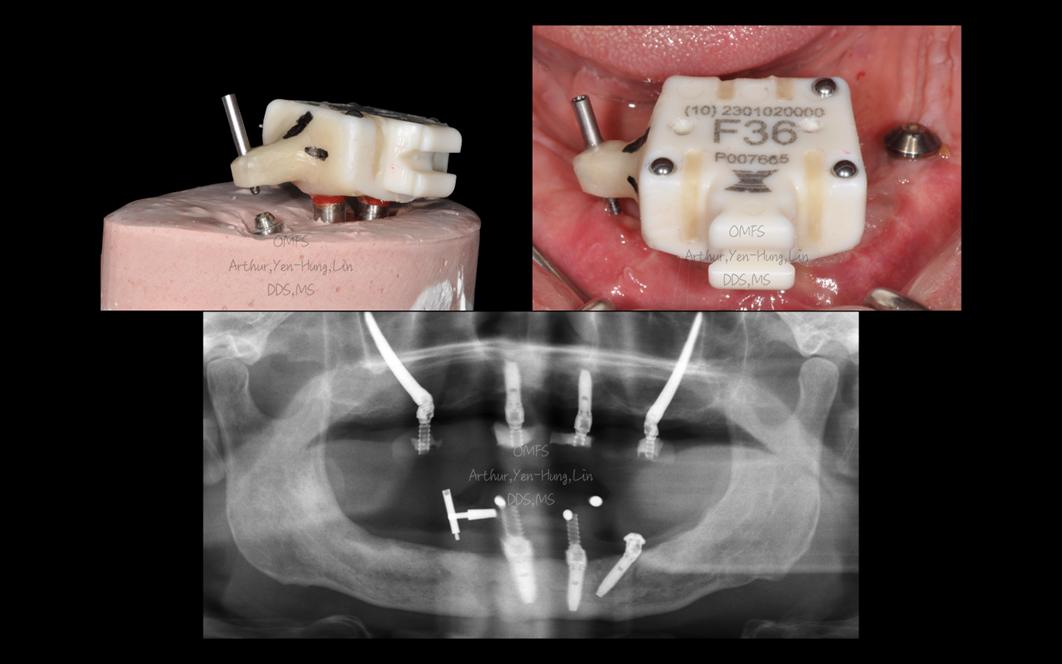

1) 客製化 X-Clip 的設計

術前請技師依「X-Clip 相對於下顎前牙兩支植體」的空間關係進行鑽孔與製作,完成可用螺絲鎖附、可重複定位的客製化 X-Clip。由於患者先前已製作臨時假牙,可直接沿用原本的模型/資料來製作 X-Clip,減少重新取模與重建流程的時間成本。

2) #45 的假牙導向規劃(prosthetically driven planning)

我們以原本的臨時假牙設計為基礎,反推 #45 的植體位置與 MUA(multi-unit abutment)方向,使術後能以最小修改方式恢復臨時假牙功能。

3) MUA screw hole 的定位

為了在手術中快速確認 MU screw hole 的方向與位置,我們請技師在規劃的 #45 區域加入一個 guide pin 的定位概念,作為術中核對方向的參考點,確保植體軸向與假牙開孔接近一致。

▍手術流程與術中重點

手術中先將客製化 X-Clip 以螺絲固定於兩支已骨整合成功的前牙植體,完成導航系統校正後,依術前規劃在 X-Guide 即時導航下進行鑽孔與植體植入。